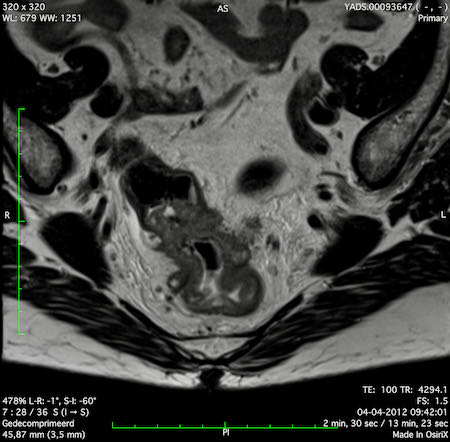

Hình ảnh

Các hình ảnh được cung cấp cho thấy ung thư biểu mô tế bào nhẫn với tình trạng dày lan tỏa thành trực tràng, hình ảnh bia bắn điển hình, và sự xâm lấn mỡ mạc treo trực tràng.